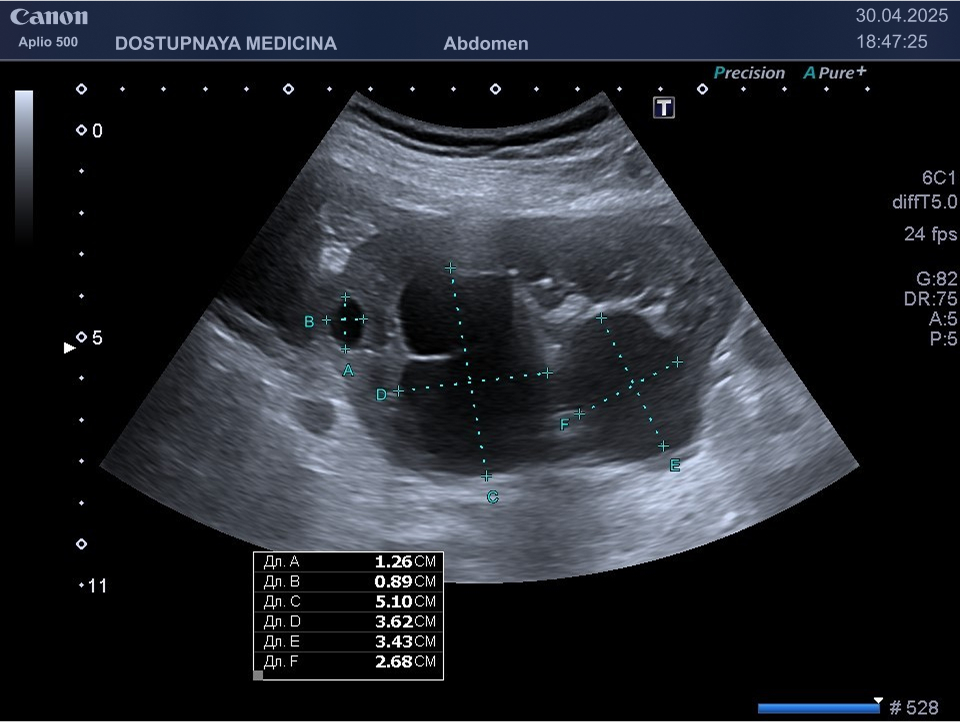

Чаще всего кисты почек протекают бессимптомно и являются случайной находкой во время ультразвукового исследования. При увеличении кисты в размерах может появиться боль в поясничной области в результате раздражения образованием нервных окончаний почки. Большая киста может сдавливать сосуды почек, приводя к нарушению кровотока в органе вплоть до полной гибели органа с развитием почечной недостаточности. Киста, локализованная в почечном синусе, может сдавить лоханку и чашечки почки, что приводит к нарушению оттока мочи вплоть до гидронефротической трансформации почки с полной утратой её функции. Поэтому очень важен периодический контроль размеров кисты не реже 1 раза в 6-12 месяцев.

Кисты небольших размеров (до 3 см), как правило, не требуют никакого лечения, необходимо лишь контролировать размеры и количество кист не реже 1 раза в 6-12 месяцев. Кисты от 3 до 5 см можно пунктировать и дренировать под контролем УЗИ с последующим введением в них склерозирующего препарата. Более крупные кисты (больше 5 см), как правило, иссекают лапароскопически. Медикаментозного лечения кист на данный момент не существует.